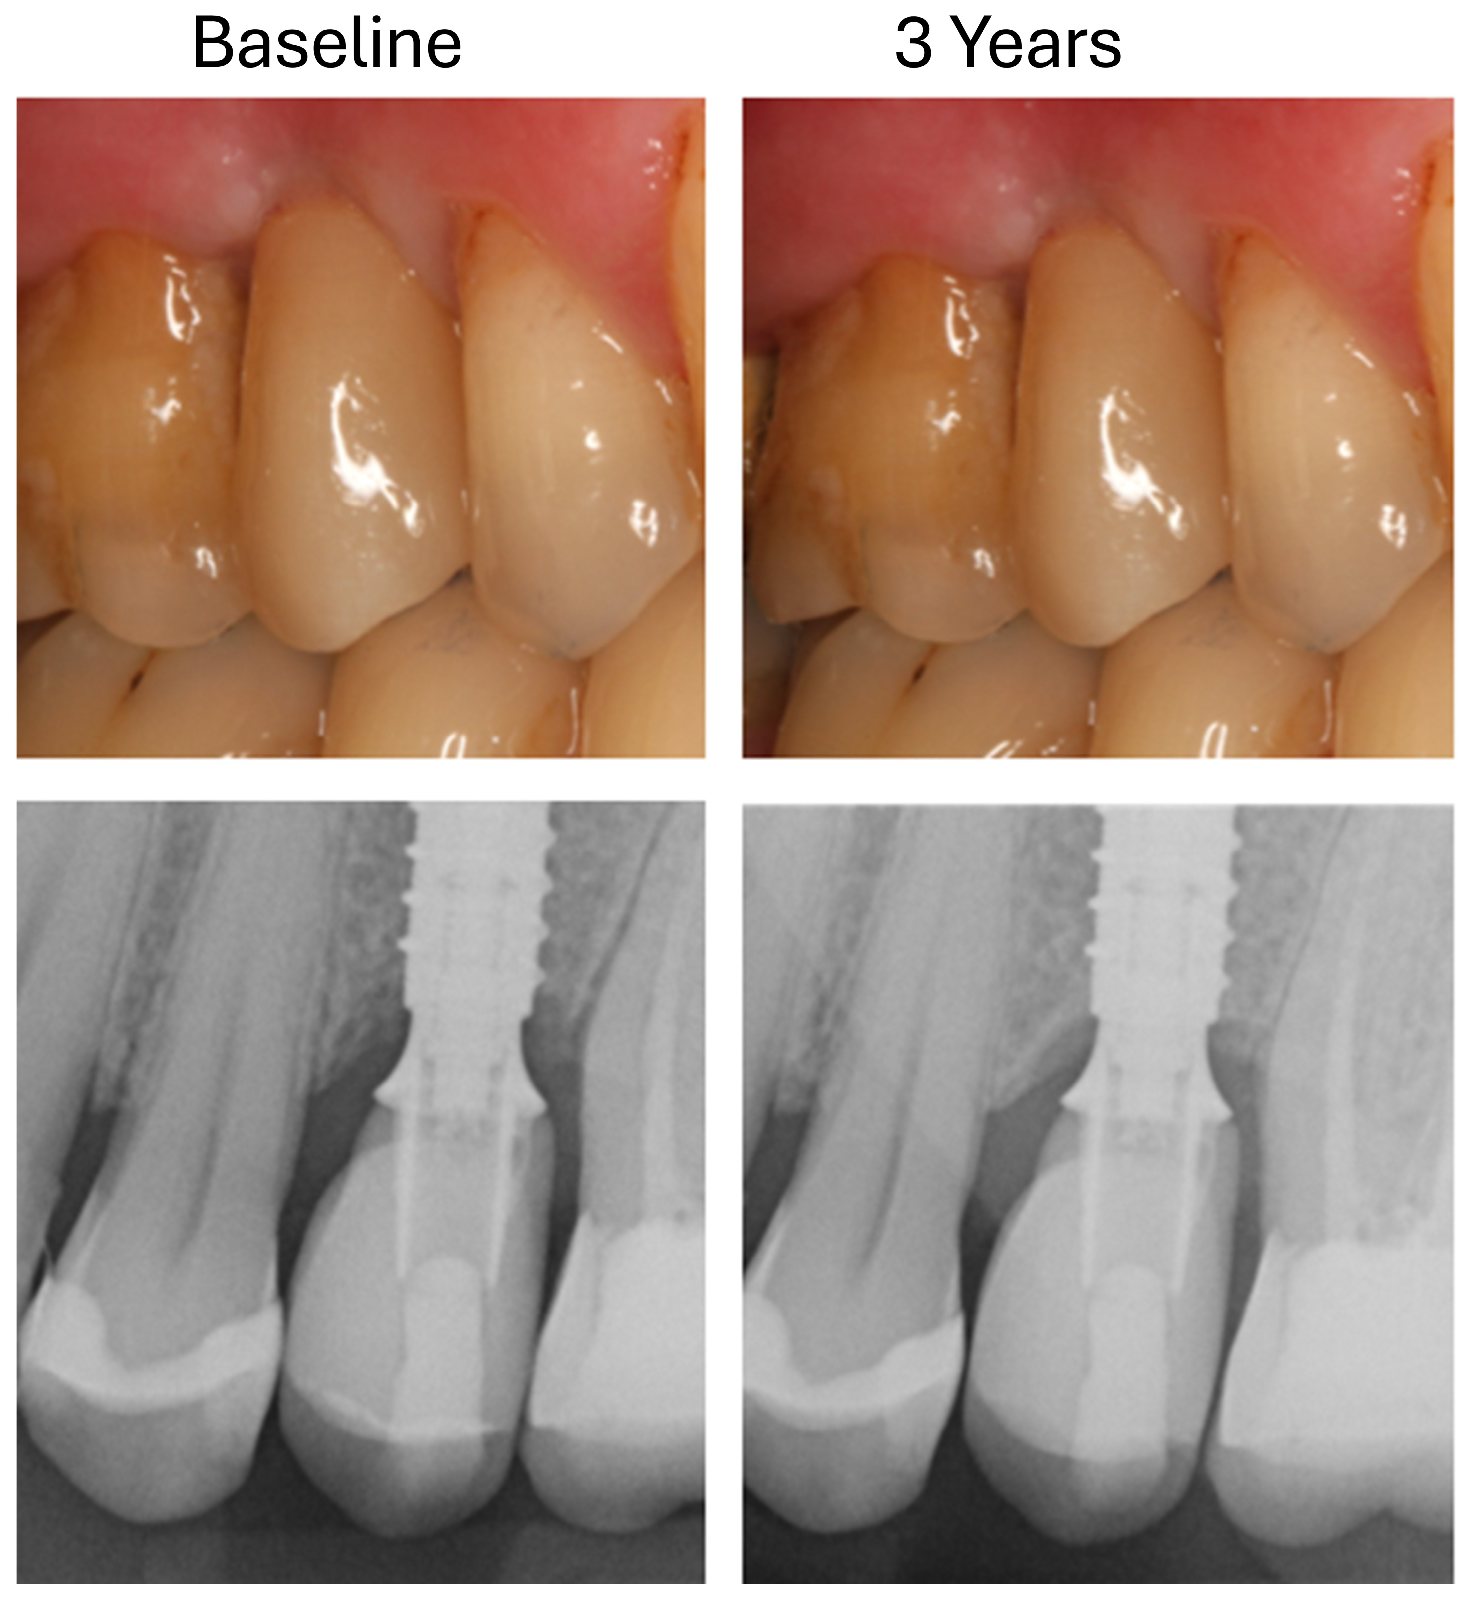

2.6. Radiological Analysis of Marginal Bone Loss

- T0: 1 week after insertion of the superstructure (baseline);

- T1: 3 years after implantation.

3.3. Changes in Marginal Bone Profile